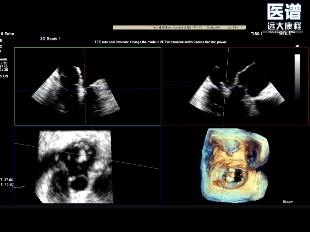

TEE-3D

TEE-3D血流